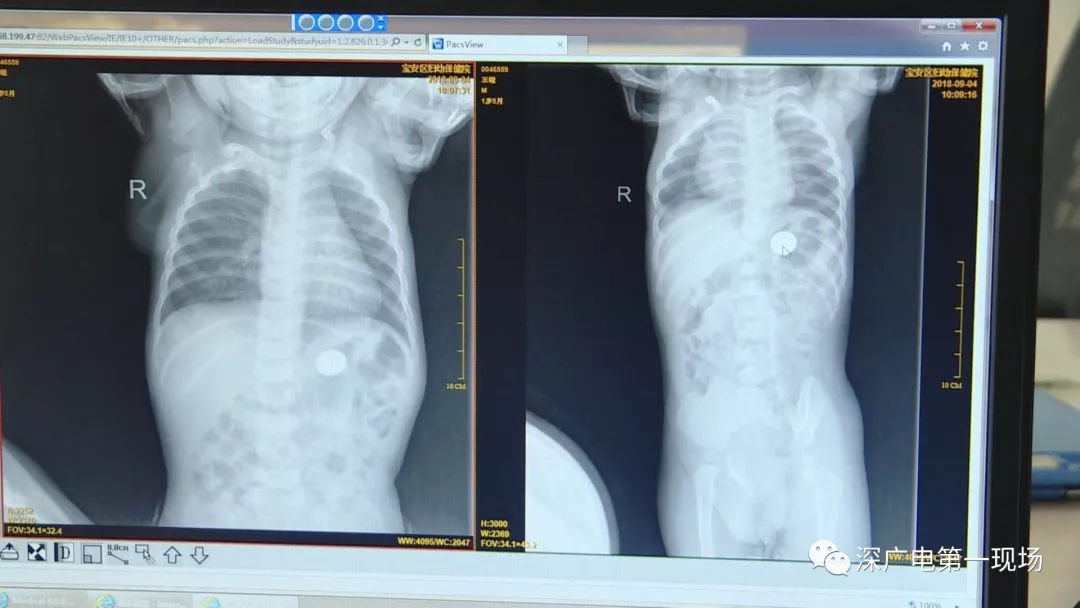

9月4號,一名1歲零5個月的男嬰因在家中摔傷,被父母送到了寶安區(qū)婦幼保健院,醫(yī)生診斷為左側尺橈骨骨折。在進行全麻手術之前,院方例行對嬰兒進行了周身檢查。手術前,兒外科醫(yī)生趙冠聰在查看患者的胸片時,發(fā)現(xiàn)這名嬰兒的胃部有一枚硬幣大小的暗影。

經(jīng)過兩個小時的時間,兒科醫(yī)生郭景濤為患兒取出了藏在胃底的一角錢硬幣。目前,患兒已經(jīng)痊愈出院。